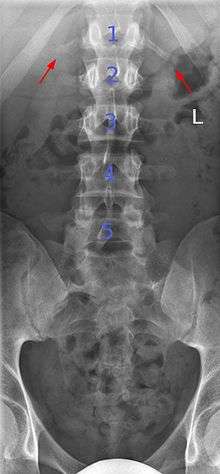

Several congenital block vertebrae in the transition from the thoracic to the lumbar spine and hemivertebrae.